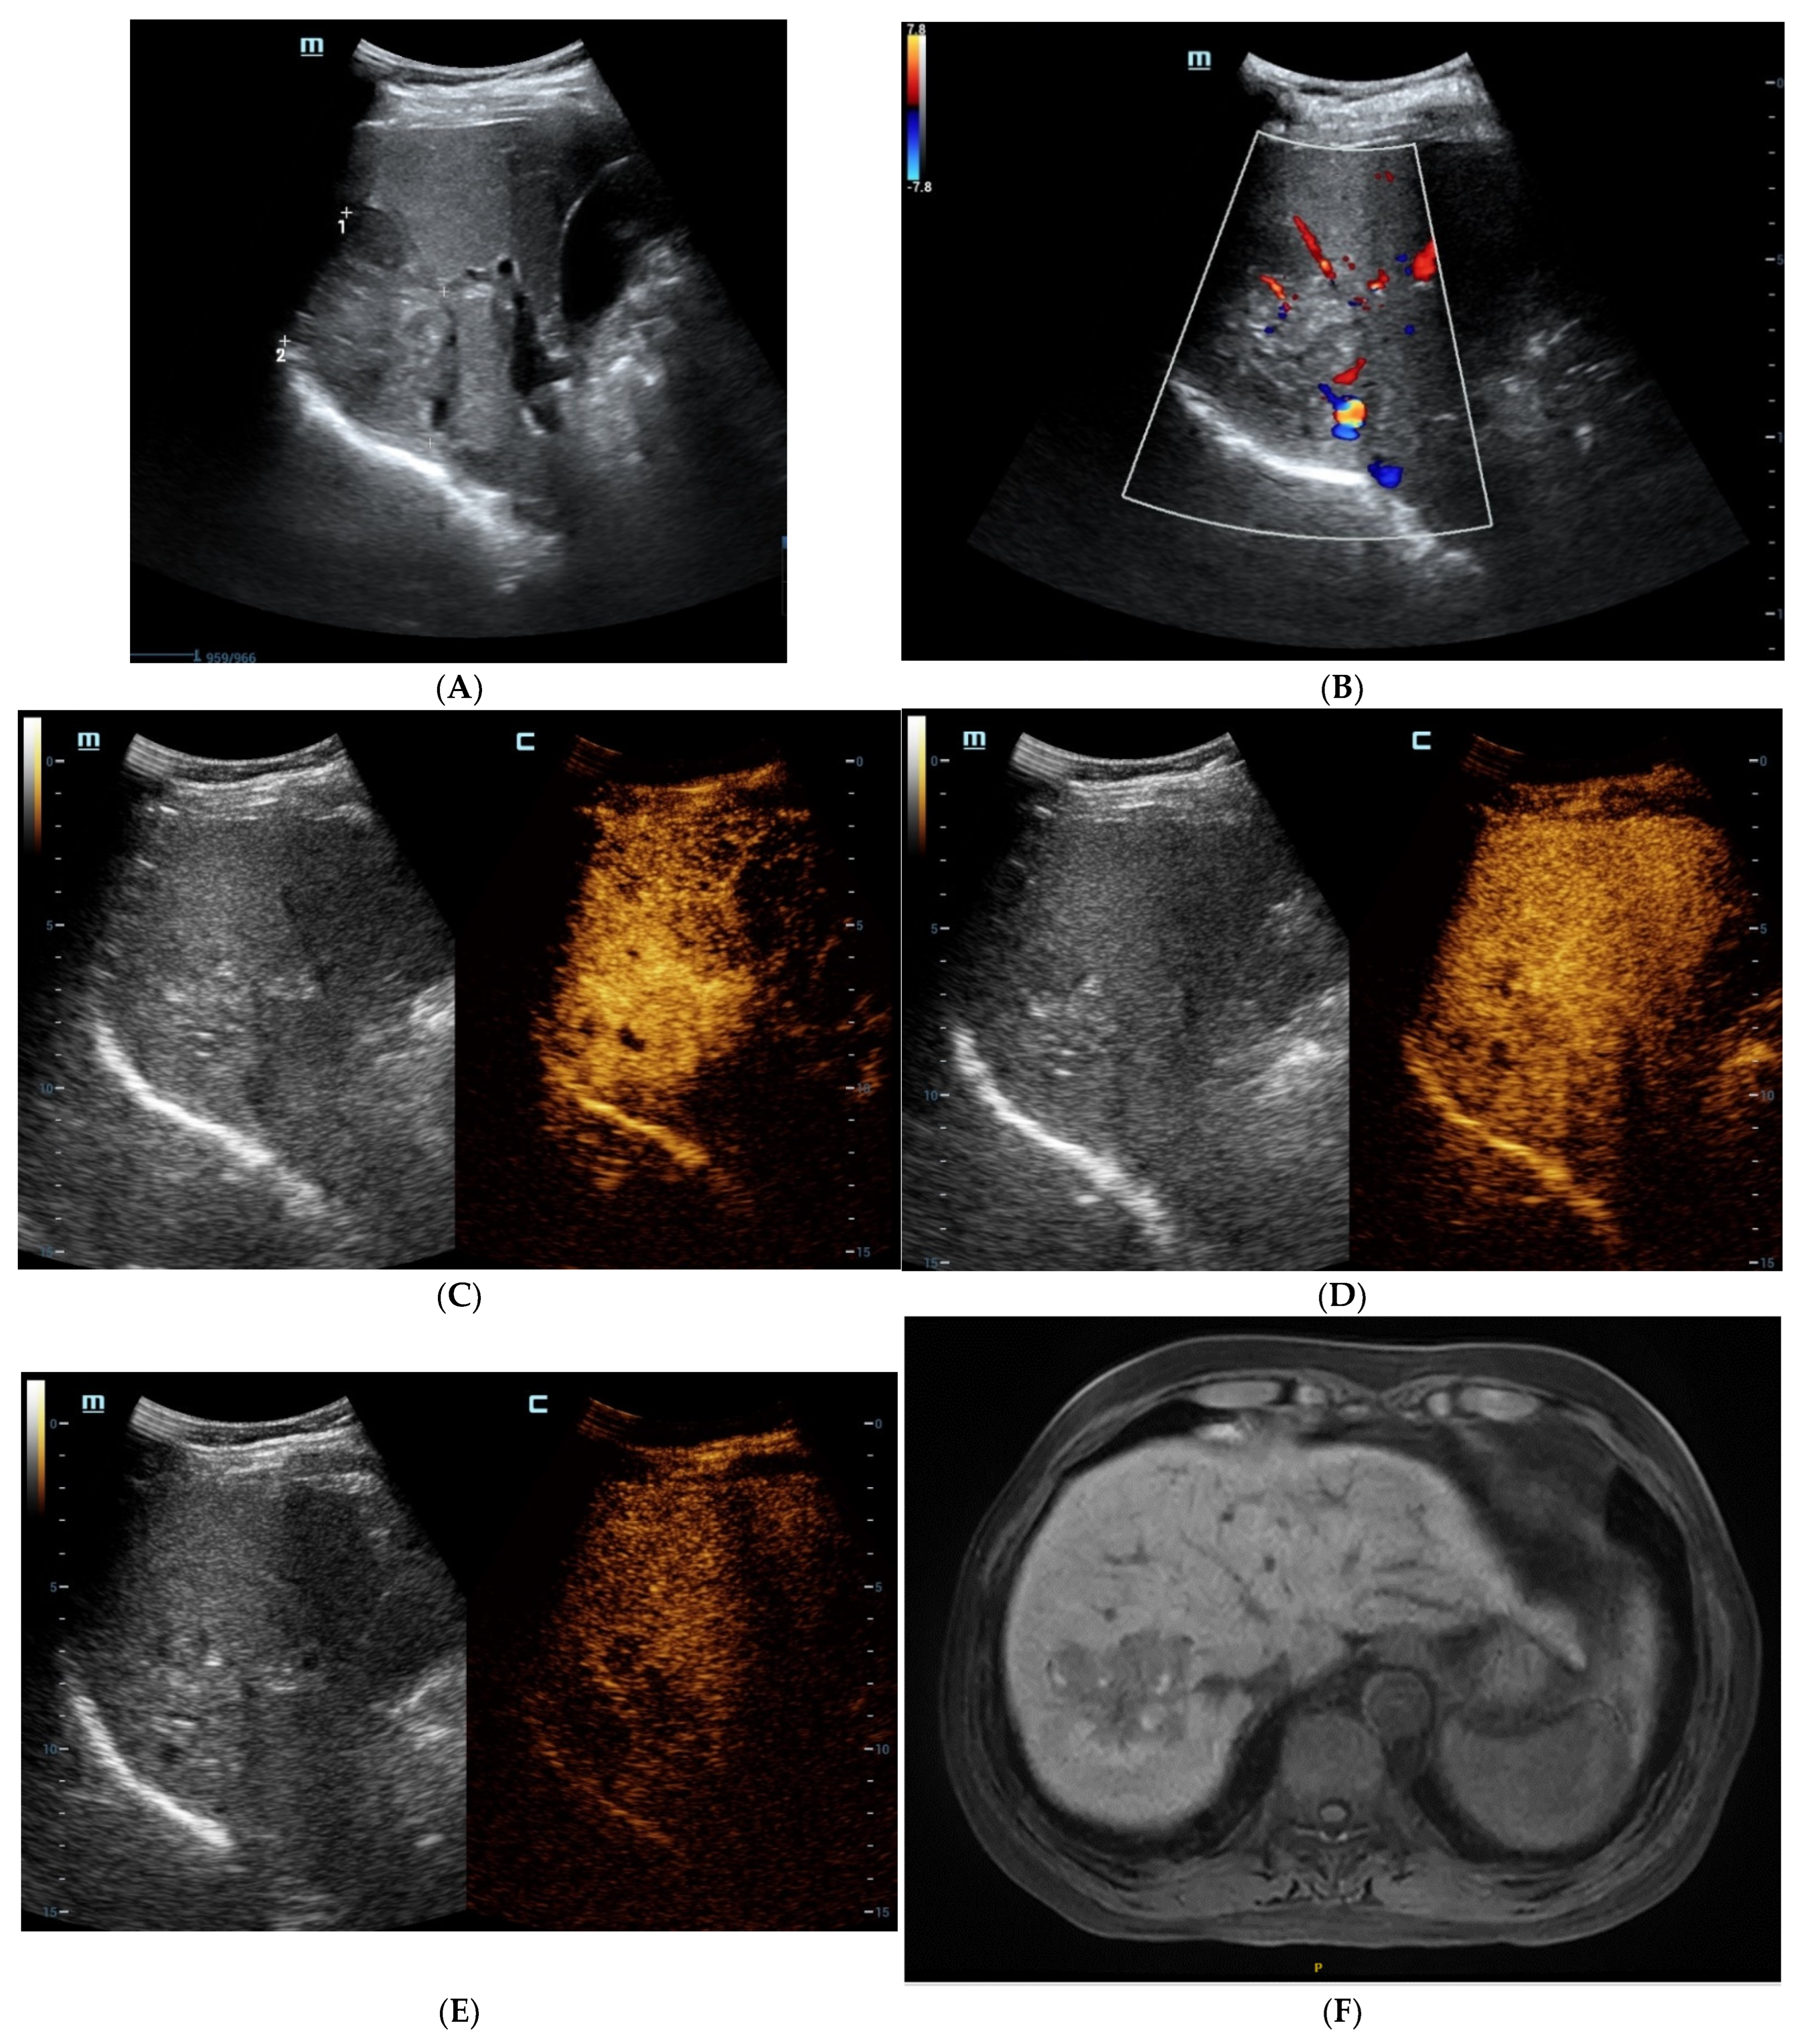

Figure 1.

The contrast-enhanced ultrasound (CEUS) and contrast-enhanced magnetic resonance imaging (CEMRI) of steatohepatitic hepatocellular carcinoma (SH-HCC). A heterogeneous hyperechoic le-sion was detected in the right lobe of the liver (A). Short linear blood flow signals were seen in the peripheral of mass (B). As seen via CEUS, the hepatic nodule did not show rim, peripheral dis-continuous or heterogeneous hyperenhancement in the early arterial phase (C). During the portal venous phase, it was continuous iso-enhancement (D). It exhibited mild washout in the late phase (E). The hepatic lesion was heterogeneous hypointense on T1WI (F). A signal drop in the T1WI opposed-phase was observed (G). It was marked as hyperintense on unenhanced T2WI (H). After injection of contrast agent, the hepatic lesion showed non-rim hyperenhancement in the arterial phase (I). It became hypo-intensity during the late phase (J).